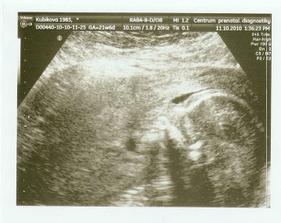

11.10. Velký UTZ dopadl dobře, sice to trvalo dýl, asi hodinu jsme pochodovali po chodbě, aby se nám mimčo ukázalo, bylo totiž zády...hold je to naše stydlivka 🙂